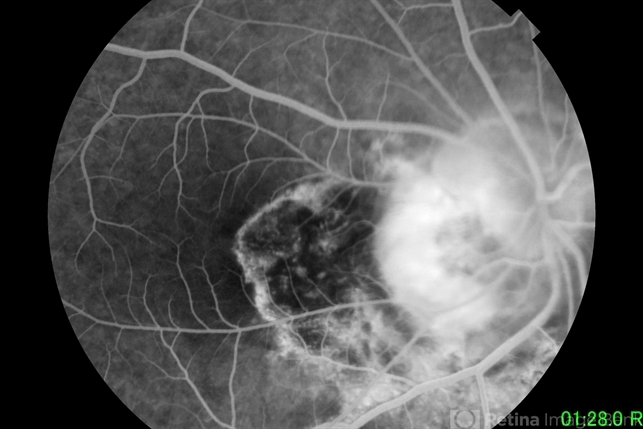

- optic nerve coloboma

- 19 year old male patient seen on routine examination for refraction. Had blurring of vision on the right eye since childhood. Was initially seen by a general ophthalmologist who diagnosed the patient with glaucoma. Present vision is CF at 3 feet uncorrected, and 20/400 with a refraction of -8.00 -1.50 X 180.